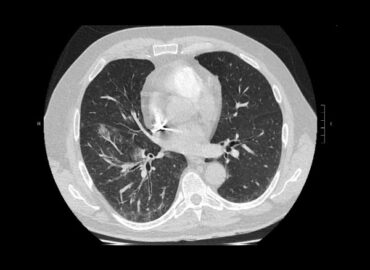

Paciente de sexo masculino de 68 años de edad, que consulta disnea CF III y tos con expectoración sanguinolenta […]

Hemoptisis